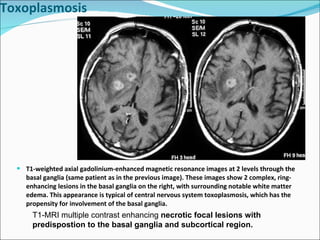

T1-weighted axial gadolinium-enhanced magnetic resonance images at 2 levels through the basal ganglia (same patient as in the previous image). These images show 2 complex, ring-enhancing lesions in the basal ganglia on the right, with surrounding notable white matter edema. This appearance is typical of central nervous system toxoplasmosis, which has the propensity for involvement of the basal ganglia. Toxoplasmosis T1-MRI multiple contrast enhancing  necrotic focal lesions with predispostion to the basal ganglia and subcortical region.

T1-weighted axial gadolinium-enhancedmagnetic resonance images at 2 levels through the basal ganglia (same patient as in the previous image). These images show 2 complex, ring-enhancing lesions in the basal ganglia on the right, with surrounding notable white matter edema. This appearance is typical of central nervous system toxoplasmosis, which has the propensity for involvement of the basal ganglia. Toxoplasmosis T1-MRI multiple contrast enhancing necrotic focal lesions with predispostion to the basal ganglia and subcortical region.